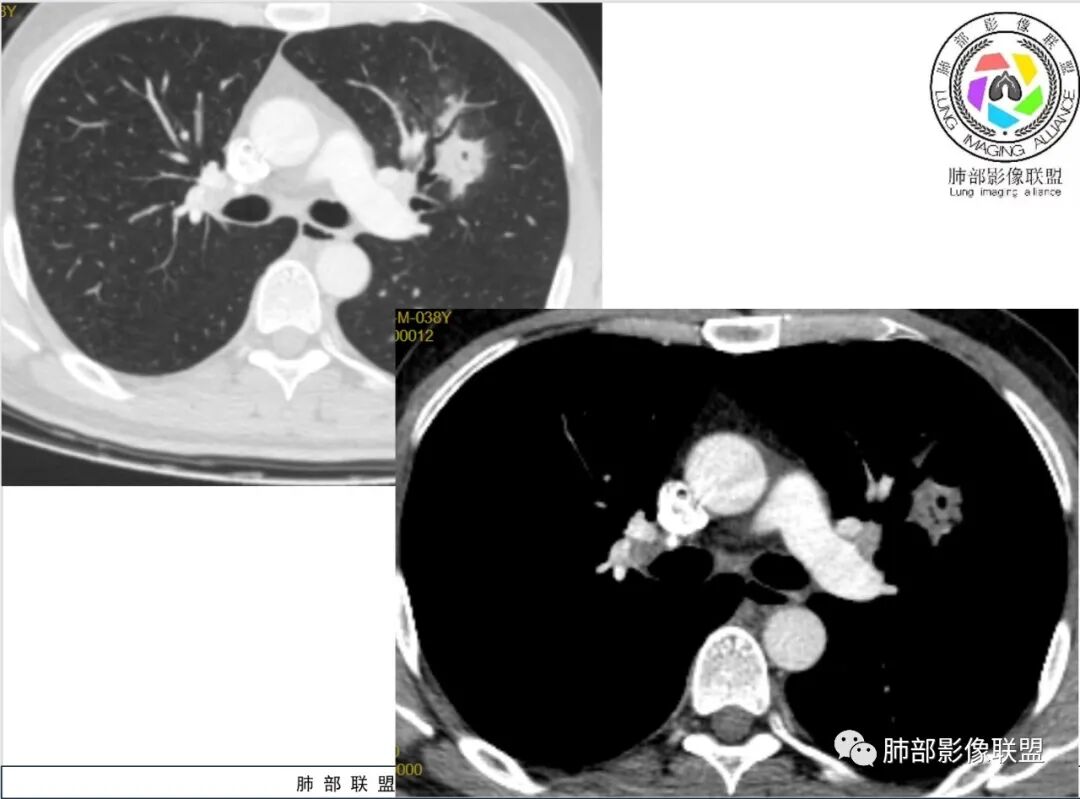

谢加平:左肺上叶和右肺下叶见多发散在性斑块病灶,边界清楚,部分见U形凹陷和刀切征,周围见模糊晕征,近胸膜下分布和蘑菇兄弟特点,累及左肺上叶上舌段支气管牵拉性扩张,前后13天复查整体病灶吸收不明显,有机化趋势表现,首选炎性肉芽肿(隐球菌感染?),请结合隐球菌荚膜抗原检查。

影像:左肺上叶、右肺下叶团片病灶,右肺下叶有结节病灶,病灶内支气管僵硬,稍扩张,强化有死

蓝天白云:两肺多发斑片状影,晕,内见扩张支气管影,可见直边,轻度延迟强化,纵隔肿大淋巴结,考虑炎性肉芽肿,隐球,淋巴瘤。

丽:双肺散在片状及结节状高密度影,边缘模糊,支气管穿行,走形僵硬,不均匀强化,考虑:OP,鉴别隐球菌,淋巴瘤。

小兜:男性,39岁,3周前劳累受凉史,次日至三亚开始咳嗽咳痰,入院时自述症状减轻。CT示双肺多发斑片影,部分病灶内部支气管壁增厚扩张穿行,平扫密度均匀,增强未见明显坏死,治疗前后部分病灶略吸收。实验室检查白细胞血沉轻度增高。考虑隐球菌感染可能,鉴别类鼻疽,淋巴瘤。

尘缘:中年男性,咳嗽咳痰伴乏力多汗,无发热,偶有畏寒。期间至某中医院治疗服中药后,症状好转。白细胞与血沉稍高。影像表现:左上肺团块状影(增强后CT值约22,伴有血管漂浮),中间支气管明显扩张,伴有小空洞形成,周围有晕,右下肺多发团块状影(增强后CT值约48),无明显支扩,伴胸膜下多发小结节,13天后复查,左上肺主病灶无明显变化,其他病灶范围有缩小,空洞消失,右下肺病灶变化不明显。

2、影像资料:双肺多发的小结节、斑片状及不规则型的实性病灶,周围有晕,沿支气管血管束分布,部分的病灶周围可见磨玻璃样影、支气管的扩张以及小的空洞。增强扫描病灶,轻度强化内部见支气管造影征。部分的病灶,支气管有扩张,内壁凹凸不平的改变,纵隔淋巴结未见肿大。病灶整体的形态还是多样化,部分位于胸膜下。